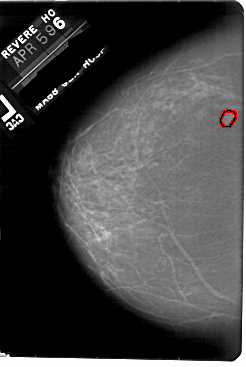

A_1855_1.LEFT_CC

LEFT_CC LINES 5491 PIXELS_PER_LINE 3676 BITS_PER_PIXEL 12 RESOLUTION 43.5 OVERLAY

FILE: A_1855_1.LEFT_CC.OVERLAY

TOTAL_ABNORMALITIES 1

ABNORMALITY 1

LESION_TYPE MASS SHAPE OVAL MARGINS OBSCURED

ASSESSMENT 3

SUBTLETY 3

PATHOLOGY BENIGN

TOTAL_OUTLINES 1

BOUNDARY